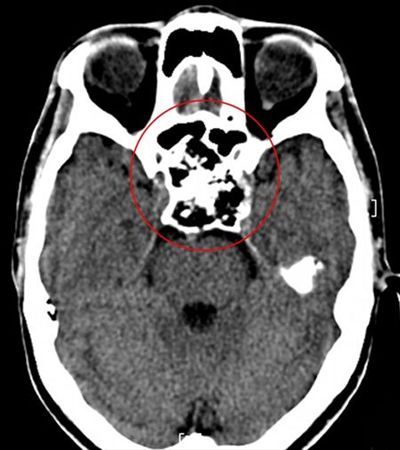

【影像表现】:CT平扫见蝶窦、斜坡巨大骨质破坏区,膨胀性生长,周围似有一完整的骨壁,密度混杂。

【影像诊断】:蝶窦、斜坡及鞍上骨软骨瘤。